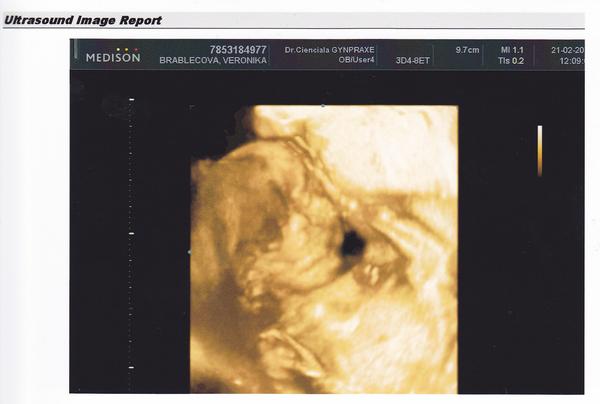

@lucikk1 @suzik161 holky díky moc.... já jsem celá z toho v prdeli 😀 😀 fakt to se ani popsat nedá 🙂 hooooodně moc vám to taky přeju zažít, ale taky se dočkáte, nebojte nic. A jak tam má ty ruce a nožky fajné na té první fotce, no krása.... no a tak jsem byla naměko dneska, že jsem si řekla, že když už se chlapovi nevyplnil ten kluk, tak že aspoň bude jméno, jaké se mu nejvíce líbí... takže s největší pravděpodobností to bude Eliška 🙂